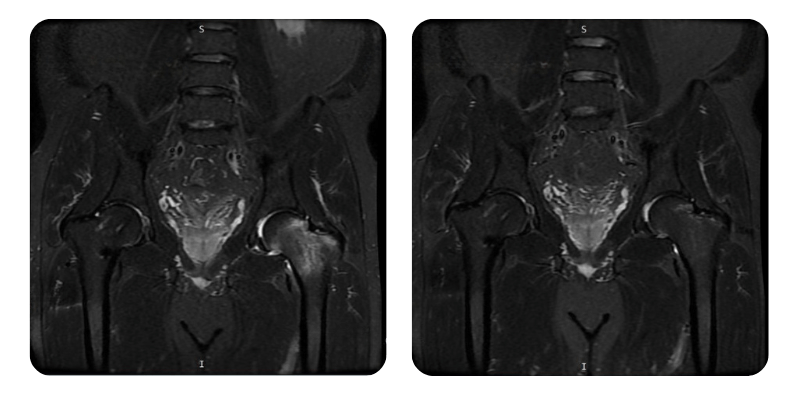

Előtte

Utána

B.A.M., 56 éves – Avaszkuláris nekrózis a bal combfej és combnyak területén, jobb combnyaktörést követően

Diagnózis: Avaszkuláris nekrózis a bal combfej és combnyak területén, jobb combnyaktörést követően.

Terápiás beavatkozások: 20 alkalom hiperbár oxigénterápia.

Lefolyás: A 20 hiperbár kezelést követően a páciens állapota körülbelül 90%-os javulást mutatott, a derék- és csípőtáji fájdalmak teljesen megszűntek. Mozgékonysága jelentősen javult, nincs éjszakai fájdalom, és nincs szükség további beavatkozásokra.